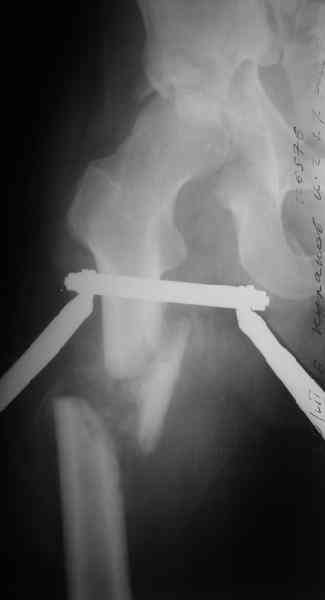

Здравствуйте Анатолий Федорович. Сегодня заситезировали этопу пациенту длинные трубчатые кости. В отношении вертлуги мы остановились на остеосинтезе вертлужной впадины из доступа Кохер -Лангенбек. Необходимость (и возможность) закрытого вправленя через месяц представляется сомнительной - даже если удастся - судьбу головки

это вряд ли изменит в лучшую сторону, а если вправить, то на нее будет осуществляться давление отломком,связанным с осевым скелетом. В дальнейшем, если возникнут ожидаемые проблемы с АНГБ, коксартрозом, вернямся к этому больному. (описанную вами операцию надо хоть посмотреть разок, наверняка есть какие-нибудь тонкости).